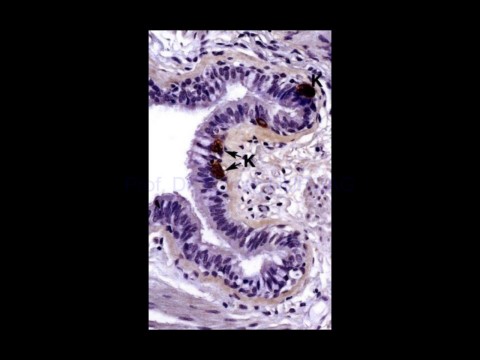

Page 27 - Solunum Sistemi

02-Dec-20                                     Solunum sistemi histolojisi,                                                 27